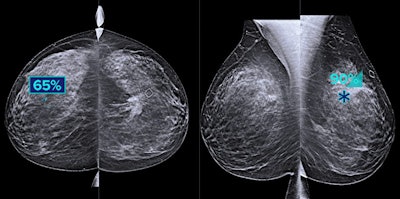

Hologic's Genius AI software highlights suspicious areas of interest on breast tomosynthesis exams. Image courtesy of Hologic.

Hologic's Genius AI software highlights suspicious areas of interest on breast tomosynthesis exams. Image courtesy of Hologic.Running on the acquisition workstation of the mammography system without the need for a server, the deep-learning software delivers key metrics to radiologists to help them categorize and prioritize cases by complexity and expected reading time, according to the vendor. Hologic said studies have shown that Genius AI is more accurate than its previous-generation computer-aided detection software.

Hologic garnered FDA clearance for Genius AI in late 2020.